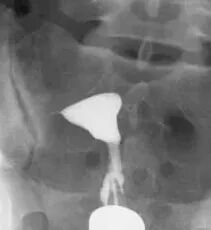

实时动态子宫输卵管碘油造影是将传统的造影改良,使患者无痛,将球囊导管置入宫颈内口,注入液体充盈球囊堵住宫颈内口后,将碘化油经导管缓慢注入宫腔,在X光透视下,动态观察碘油逐渐膨胀宫腔,流入输卵管,经伞端流入盆腔的全过程。在操作后的12~24小时,再拍一张延迟涂抹片,观察碘油在盆腔内的弥散情况。

如下图所示,这是一张正常的延迟涂抹片,碘油在盆腔内均匀弥散。